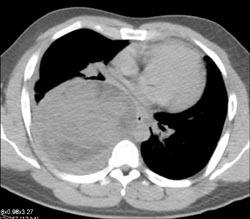

Increased Pulmonary Blood Flow to Lower Lung Fields